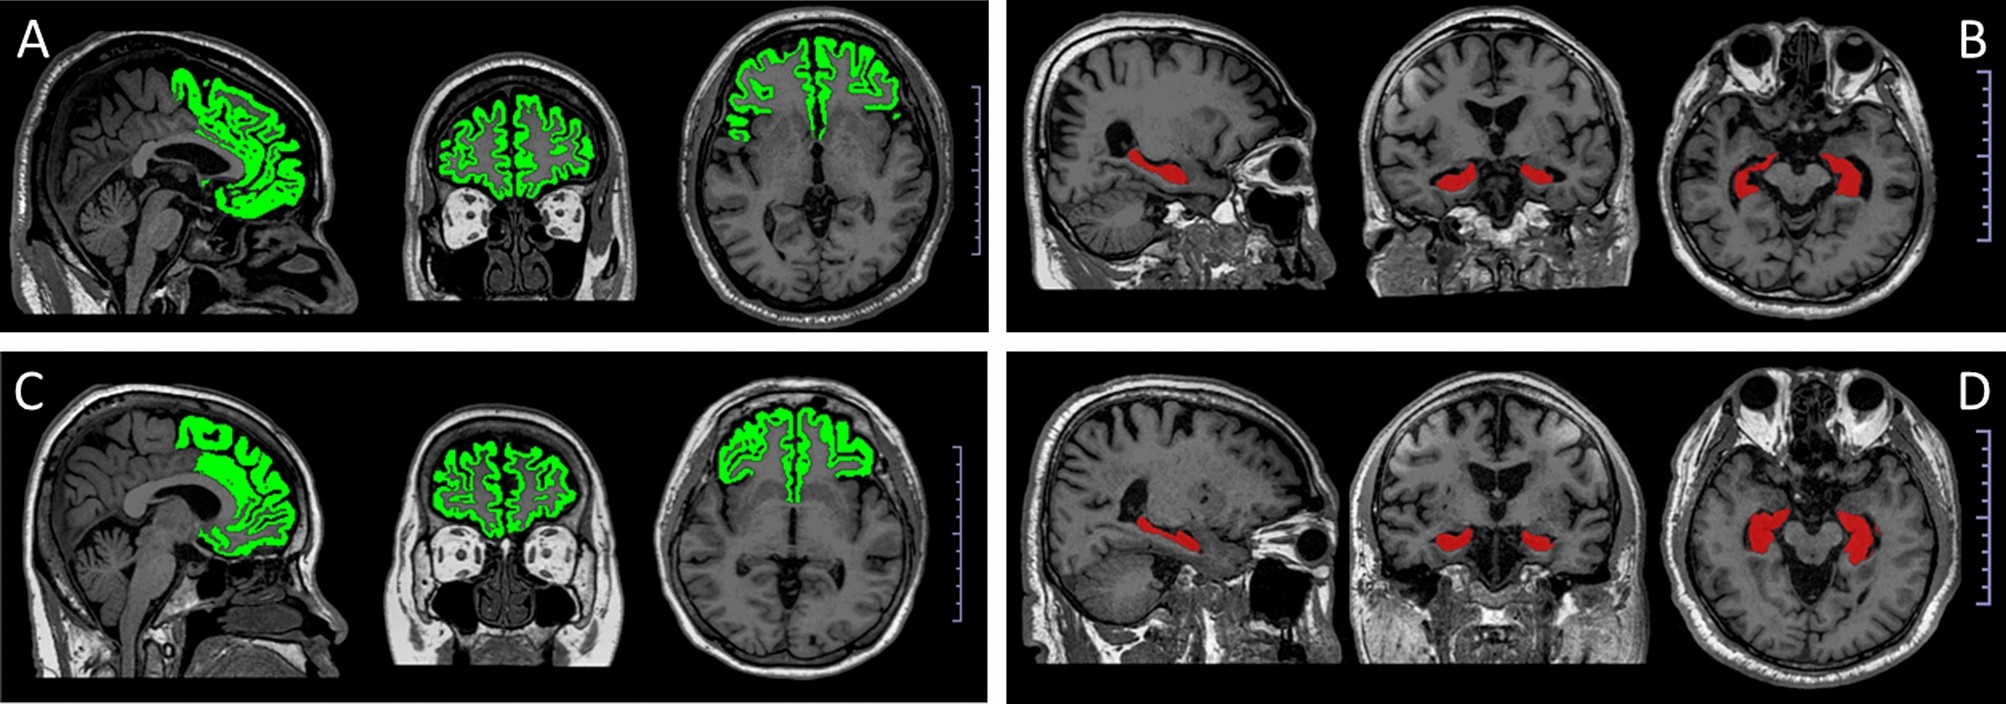

Figure 1

Representation of MRI brain images of participants, the prefrontal cortex identified in green and the hippocampus in red (scale bar, 1 cm × 10 scale); (A) the brain of a 59-year-old man with a MoCA score = 25, total prefrontal cortex percentage = 26.9 and circulating lipocalin level in 2020 = 8.59 ng/ml; (B) the brain of a 65-year-old man with a MoCA score = 27, total hippocampus percentage = 0.6 and circulating lipocalin level in 2020 = 21.15 ng/ml; (C) the brain of a 60-year-old man with a MoCA score = 24, total prefrontal cortex percentage = 23.4 and circulating lipocalin level in 2020 = 21.98 ng/ml; (D) the brain of a 60-year-old man with a MoCA score = 25, total hippocampus percentage = 0.49, and circulating lipocalin level in 2020 = 13.07 ng/ml.